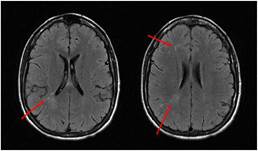

El estudio vascular, el electroencefalograma y el líquido cefalorraquídeo (LCR) fueron normales. La resonancia magnética nuclear (RMN) mostraba lesiones hiperintensas en T2 en sustancia blanca de hemisferio derecho sin restricción en difusión ni captación de contraste (fig. 2). Analíticamente destacaba PCR 13,3mg/dl, ANA 1/160 patrón moteado y negatividad de otros anticuerpos.

En las pruebas complementarias destacan las de imagen con hallazgos anormales en el 83% de las tomografías computarizadas (TC) craneales y el 84% de las RMN6. En estos casos, la RMN muestra calcificaciones, atrofia o hiperintensidades en T2 en sustancia blanca subcortical, cuerpo calloso, ganglios basales y tronco, habitualmente ipsilaterales a la lesión cutánea, con frecuencia subclínicas. Las lesiones fueron generalmente unilaterales e ipsilaterales a la lesión cutánea, sin embargo, se han descrito casos con lesiones bilaterales en la imagen7. No se han descrito modificaciones de las lesiones a lo largo del tiempo con estas técnicas de imagen9. El electroencefalograma se mostró anormal en el 67,7% de los casos6. Se ha descrito la anatomía patológica de un caso que precisó lobectomía por mal control de la actividad epiléptica10. En las muestras se describe daño endotelial de la microvasculatura mediado por complemento, aunque su fisiopatología no ha sido determinada5)-(7.